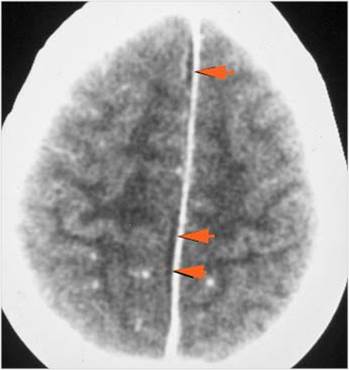

There is evidence of thrombus, thrombophlebitis or other occlusive or inflammatory process of the cortical veins, sphenoparietal sinus or sagittal sinus. [Yes/No]

There is brain edema specifically involving the frontal and temporal lobes. [Yes/No]

There is cerebritis specifically involving the frontal and temporal lobes. [Yes/No]